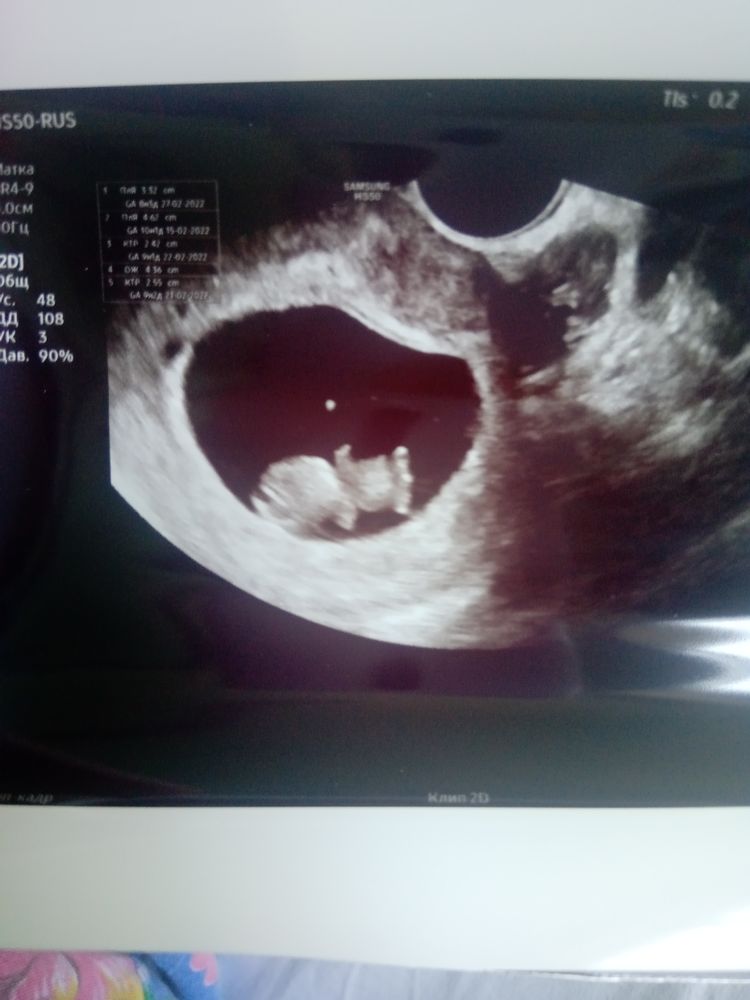

Всё о нашей беременностиНам уже 10 недель... Сегодня утром собираясь на работу, обнаружила мазню розового цвета.. Я в шоке.. Полетела в стационар.. И недели не прошло после выписки... 🤦♀️Но чтобы не ждать часу дня, сходила платно на узи.. На узи всё хорошо 👏... Малыш активный.. Мы уже 3см.🥰Узист сказал, что похоже у нас мальчик... Увидел половой орган.. Но это ещё под вопросом...Но пришлось лечь в стационар.. Теперь мазня коричневая-не много... Что за беда 🤦♀️ 😭... 18го уже надо ехать на первый скрининг... В понедельник уже встала на учёт 👏... После подсадки, должна была 4го сентября ехать к своему репродуктологу в город, чтобы там ещё быть под наблюдением.. А я с больницы не вылезаю🤦♀️.. Перезаписалась на 4е октября, и опять загремела в больницу 🤦♀️

Смотрите на фото, вот, говорит, писюнчик торчит.

А там хвостик еще, половой бугорок формируется позже))))